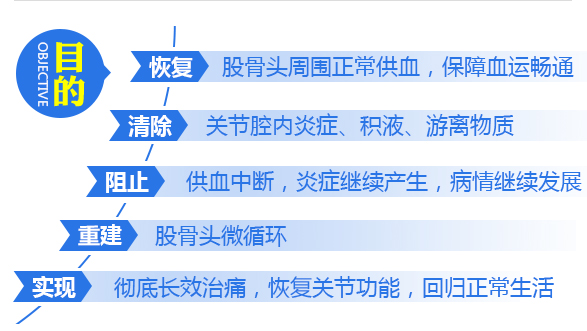

全面恢复供血原因

通过五维层级递进供血,全面恢复股骨头周围供血,打通供血,药物、营养通道,疼痛症状消失、关节受限解除;达到从根源上终止疾病发展,阻断病情反复的目的。

修复坏死骨质原因

清理、修复受损骨质,促进新骨再生